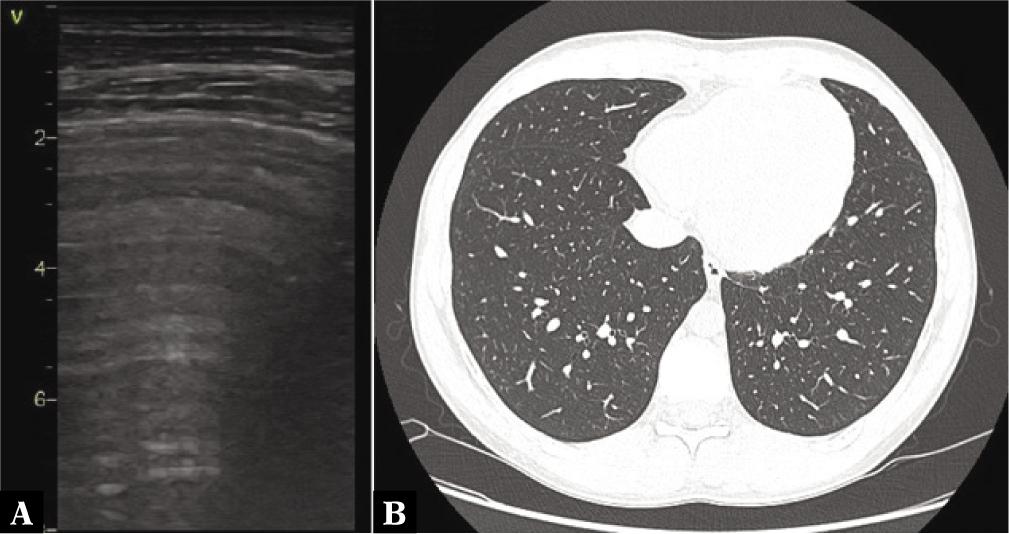

Fig. 1.

Pattern of changes visible on LUS

| Number of areas with A-line pattern (only) | 265 (61%) | 36 (64.3%) | 151 (63.4%) | 73 (57.9%) | 5 (35.7%) |

| Number of patients with dominant A-line pattern* | 24 (77.4%) | 4 (100%) | 14 (82.6%) | 6 (66.7%) | 0 (0%) |